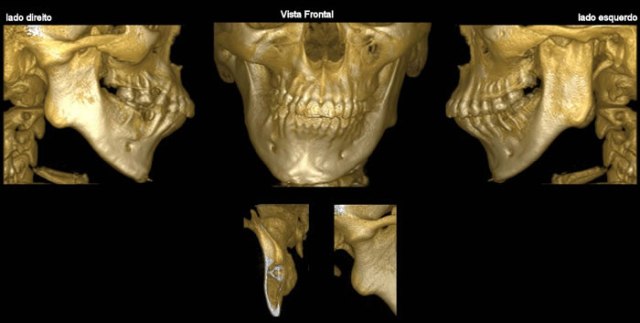

* ATM

Visualização dos componentes ósseos com a maior resolução existente na atualidade.